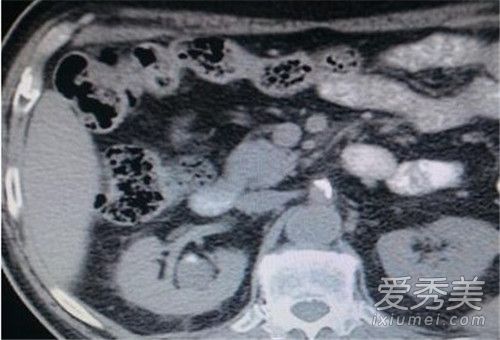

56岁的张阿姨,因右侧腰疼并持续发热了一周多去医院诊治。经他院诊断,告知需切除右肾才可痊愈。张阿姨虽知道自己患有肾结石多年,但仍不敢相信这个诊断结果,经人介绍,慕名来到武进人民医院泌尿外科求治。

记者在采访中了解到,泌尿外科医师团队迎难而上,在麻醉科、内分泌科等多科协助下,为张阿姨成功进行了腹腔镜下右肾切除术。莫乃新主任和史红雷副主任技能娴熟,很快将患者右侧病肾完整取出。剖开发现在右肾的狭小空间里,挤满了大大小小数不清的结石,密密麻麻满满一盆,有密集恐惧症的护士长直呼难以直视,不可思议。手术结束后让实习医生花了近一小时清点结石数目,不得了,2980颗!